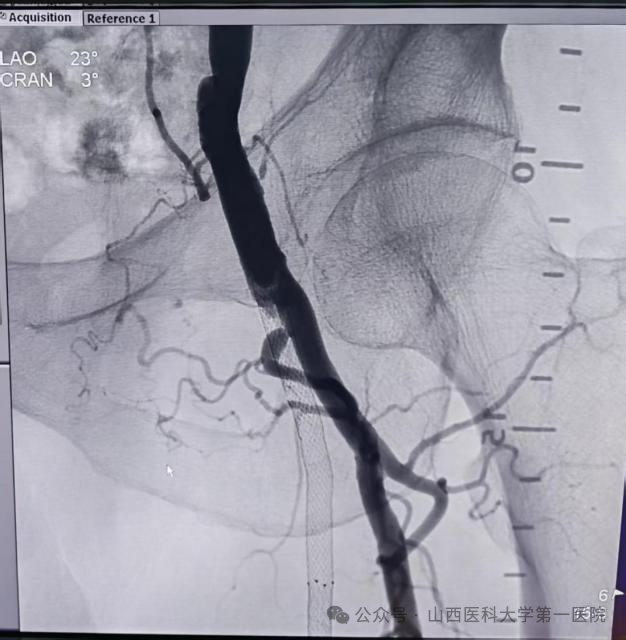

旋切术中动脉造影:左侧股浅动脉显影

术前动脉造影:左侧股浅动脉支架内无血流